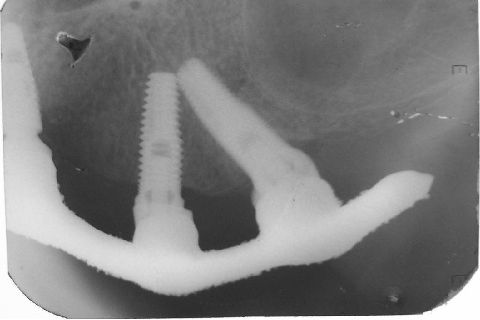

Atualização do caso clínico que já postei, "REABILITAÇÃO EM MAXILA ATRÓFICA COM IMPLANTES", um caso que inclui expansão do rebordo estreito com cinzel e martelo, expansores rosqueáveis, enxerto e instalação dos implantes distais inclinados tangenciando seio maxilar. Inclui esvaziamento do forame nasopalatino e preenchimento com biomaterial para instalação de dois implantes próximos dele. Cirurgia realizada em única sessão, com instalação dos 6 implantes. Para os colegas que não conheceram e/ou esqueceram da apresentação, este é o resumo do caso na fase cirúrgica.http://www.youtube.com/watch?v=BtvexFexRPA&hd=1

FASE PROTÉTICA DA REABILITAÇÃO EM MAXILA ATRÓFICA...incluindo a reabertura, instalação dos minipilares e PTR provisória reembasada sobre os cilindros de proteção.